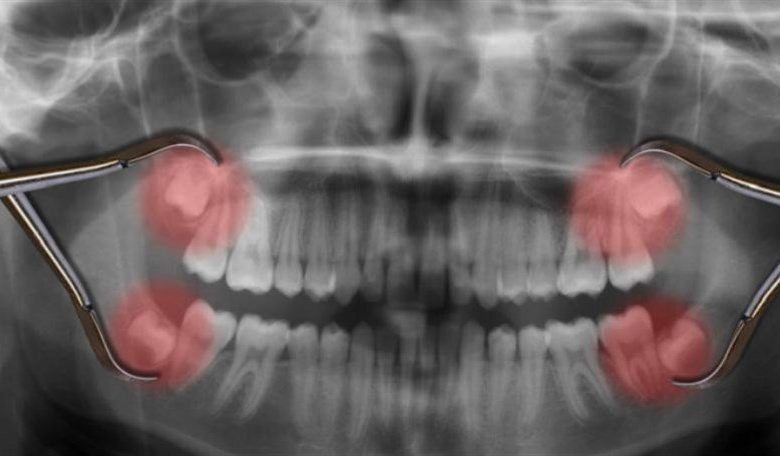

وعادة ما تظهر أشكال الأسنان البالغة التي نستخدمها لطحن طعامنا وتحويله إلى عجينة، من لثتنا على ثلاث مراحل – في حوالي 6 و12 و18 عاما.

وتحصل الرئيسيات الأخرى على أضراسها البالغة في وقت مبكر. وعلى الرغم من جميع أوجه التشابه بيننا في مراحل النمو، فإن الشمبانزي (Pan troglodytes) يحصل على أضراسه في 3 و6 و12 عاما. ويُخرج البابون الأصفر (Papio cynocephalus) آخر أضراسه البالغة بحلول سن السابعة، وقرود المكاك (Macaca mulatta) في السادسة من العمر.

ويتمثل أحد العوامل المهمة التي تقيد توقيت ظهور الأسنان، في الفراغ. إذا لم يكن الفك كبيرا بما يكفي لطقم أسنان بالغ، فلا فائدة من الضغط عليها.

وليس لدى البشر بالضبط مساحة كبيرة من الفم كما هي، مع كون ضروس العقل المتأثرة مشكلة كبيرة لجنسنا البشري. ولكن هذا لا يفسر سبب ظهورها في وقت متأخر جدا من حياتنا.

ويقول شوارتز: “اتضح أن فكينا ينموان ببطء شديد، ويرجع ذلك على الأرجح إلى تاريخ حياتنا البطيء بشكل عام، وبالاقتران مع وجوهنا القصيرة، يتأخر عند توفر مساحة آمنة ميكانيكيا، ما يؤدي إلى تأخر ظهور الأضراس”.

وتقع الأضراس الخلفية في الرئيسيات أمام مفصلي الفك الصدغيين، اللذين يشكلان معا مفصلا بين الفك والجمجمة. وعلى عكس المفاصل الأخرى في أجسامنا، يجب أن يعمل المحورين بتزامن تام مع بعضهما البعض. وتحتاج أيضا إلى نقل درجة معقولة من القوة إلى نقطة واحدة أو أكثر لتجعلك تعض وتمضغ.

ولا يوجد لدى البشر، مع وجوهنا المسطحة بشكل كبير، مثل هذا الحظ، ويحتاجون إلى الانتظار حتى تتطور جماجمنا إلى درجة أن القوى التي تضعها على كل مجموعة من الأضراس البالغة لن تضر بفكنا المتنامي.